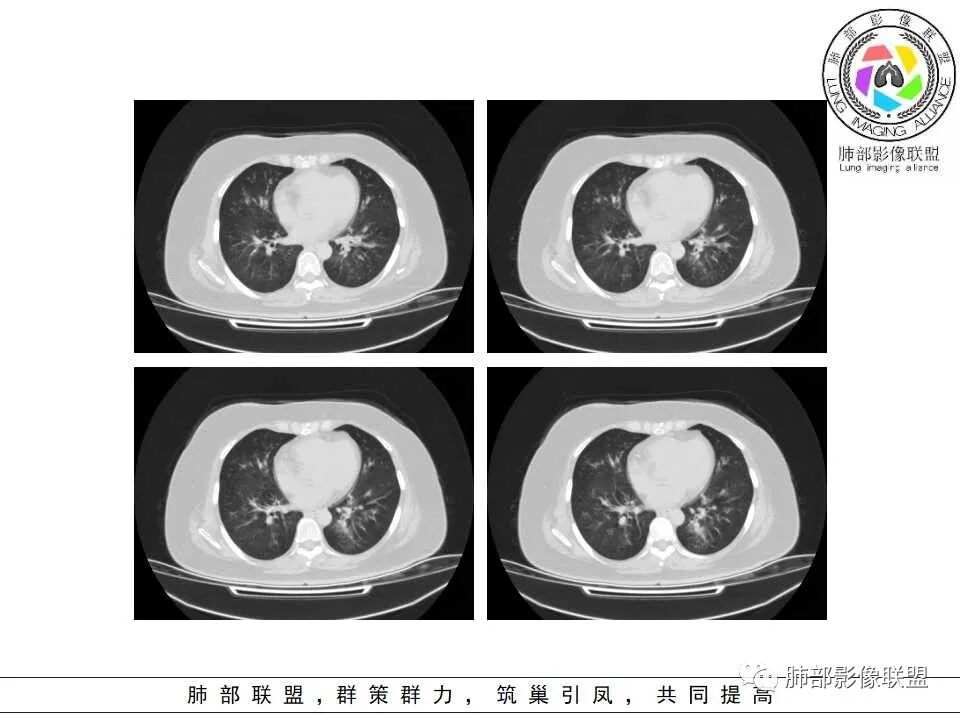

双肺支气管血管束增粗,边缘模糊呈晕状,沿中轴间质走行分布多发斑片状影,边缘模糊,糖尿病人,血象高,G实验高,气道侵袭为主,考虑曲霉菌感染,鉴别金葡

支气管来源,支气管壁增厚,树芽

影像,支气管血管束分布,支气管壁增厚,有树芽,考虑气道可能性大,血管,淋巴途径能排除?支气管镜,粘膜充血肿胀,痰多,血象高,C反应蛋白升高,快速进展呼吸衰竭,不除外感染气道侵袭性曲霉病。快速出现肾功能衰竭,非感染,血管炎是否带排。金葡菌,需要复查影像。

老年女性,发现白细胞升高两年,此次入院多次查外周血白细胞>30*10^9/L,淋巴降低,CRP显著升高,但病程中无发热,以细菌性炎不好解释;CT提示有脾大,结合外周血象,首先考虑存在血液系统疾病(白血病)基础,且未系统诊治;肺部CT提示双肺中轴间质增粗,伴随支气管管壁增厚?多发树丫及腺泡结节,部分呈点晕征,可见肺动脉分枝增粗,一元论考虑白血病肺部浸润;二院论考虑白血病并发气道侵袭曲霉。以患者病程进展看,更倾向于白血病肺部浸润。

肺动脉增粗,支气管有改变

左侧腔内有粘液栓,右侧支气管局部有扩张

支持气道病变,弥漫,支气管壁增厚,糖尿病,支持霉菌

1.病灶沿支气管分布的特点相当明显,相应支气管壁广泛增厚。这种与支气管关系极为密切的片影和/或结节影,常高度提示气道相关感染,如支气管肺炎。

2.患者两肺多发病变,具有广泛性。如此广泛分布更多见于免疫低下的机会性感染。

3.支气管壁广泛增厚对气道侵袭性曲霉病具有一定的提示意义。注意患者没有支气管扩张,临床也未提供IGE等实验室资料。

1.器官支气管管套样壁增厚和/或支气管扩张,注意壁增厚较均匀,和/或伴有播散性小片影及结节影,注意这些小片影或结节影边界有时较普通炎性病灶清楚。

2.可以阻塞支气管造成肺不张而酷似中央型肺癌。偶而可呈大范围毛玻璃样影。